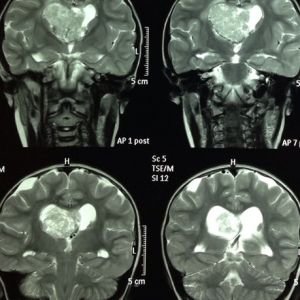

ESCLEROSIS TUBEROSA